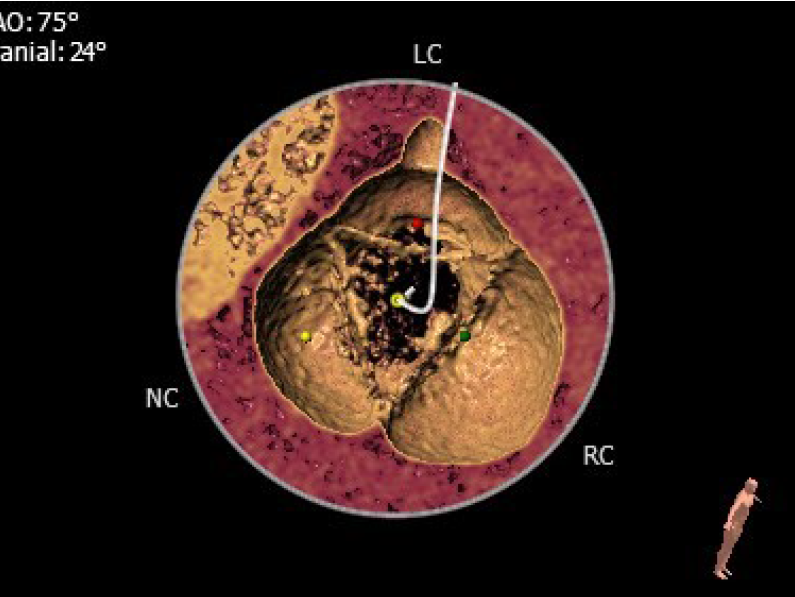

1.患者主动脉瓣三叶式,瓣叶基本等大,瓣叶增厚,瓣叶游离缘轻微钙化。

2.患者主动脉瓣环周长折算直径约25.4mm。

主动脉瓣环直径:25.4mm

左室流出道直径:24.2mm

主动脉窦部增大(右窦:44.4mm)

窦管交界扩张:49.7mm

升主动脉增宽:46.9mm

瓣叶、窦内及周围无明显钙化

主动脉瓣环平面水平夹角65°

主动脉角度指水平面和主动脉瓣瓣环平面之间的夹角。主动脉角度过大会增加TAVR手术难度,影响其手术效果。吴连拼教授团队考虑到该患者的主动脉角度偏大(65°),属于横位心,尚若采用经股路径则可能需要利用圈套器配合,保证其顺利过弓,但也很难使瓣膜位于主动脉瓣环的中央位置,这不仅增加了手术难度和时间,术后出现瓣周漏的概率也较大,于是决定使用J-Valve行经心尖TAVR。其优点在于:1)导丝顺行跨瓣,且时间短,5秒内即可完成跨瓣;2)输送路径短,只要术前在DSA下选择好经心尖路径,可以保证瓣膜较好的同轴性,同时降低了手术难度。因此J-Valve的经心尖路径在横位心患者的TAVR手术中有着无可比拟的绝对优势。

该患者为重度AR,其主动脉瓣的虚拟瓣环内径为25.4mm,按照常规J-Valve在AR时的选瓣原则(Oversize),选择外径为27mm的J-Valve较为合适。但该患者的主动脉根部较膨大(窦部最大内径为44.4mm,窦管交界平均内径为49.7mm,升主动脉平均内径46.9mm),如果选择29号的瓣膜可能使定位件的展开更为充分,进而增加其对瓣叶夹持力度。然而该患者的左室流出道内径为24.2mm,29mm的瓣膜相对过大,增加了房室传导阻滞的发生概率。因此,术前考虑到上述可能出现的情况和风险,吴连拼教授团队决定选用27mm的J-Valve作为该患者的理想介入瓣膜。术后的影像学表现也证明上述选择是正确的,即瓣膜锚定牢固,展开充分,没有瓣周漏和房室传导阻滞的发生,患者的血流动力学得到了较高的改善。